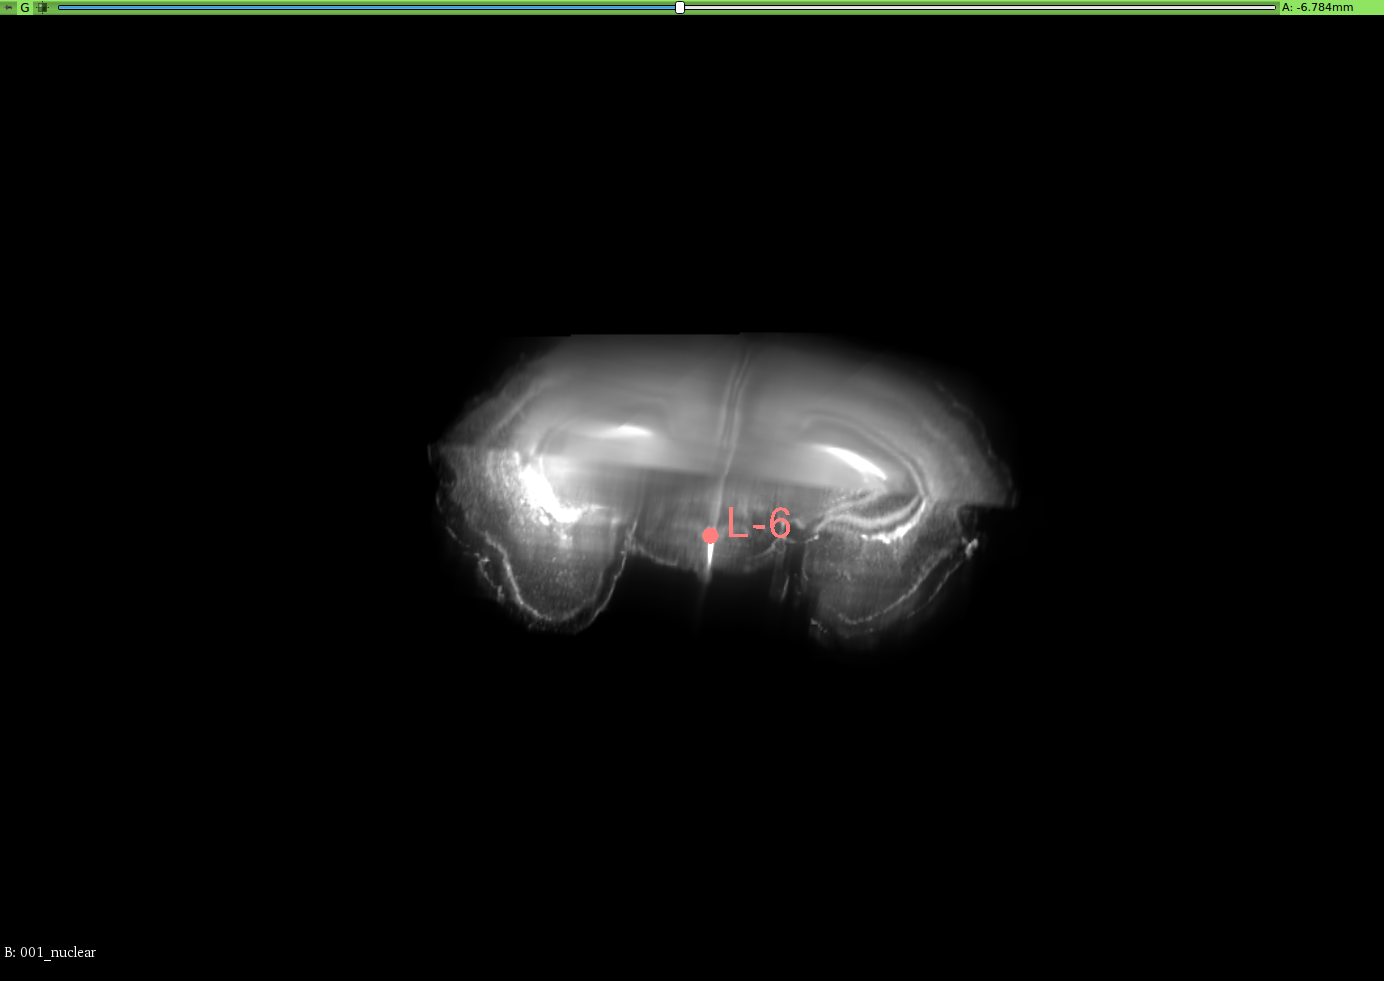

To validate the registration performance of the proposed methods and comparing the baseline methods in a more objective manner, a landmark registration test is conducted. In the CUBIC dataset, three brains are used to test the registration performance. In the landmark test, the same dataset is used for the performance validation. 12 landmarks are selected and all of these landmarks are selected where their positions vary in all three axis. 3D slicer tool is used to select the landmarks for this experiment from the CUBIC brains. A set of selected landmarks are shown in Figure 7. Table 3 shows the results of the 3D landmark registration by proposed InvGAN method and other baseline methods. The Euclidean distance between the registered landmarks and reference landmarks are presented in mm. For optimisation-based ANTS and Elastix tools, the same parameter sets are used to register landmarks selected from moving image and fixed image. After the registration, the output point locations are compared with reference point locations in the fixed image. For the deep-learning-based VoxelMorph and InvGAN, the deformation values in X,Y and Z are extracted from the same voxel location of the selected landmark’s voxel location. After applying deformation to the landmarks, the new position is compared with that of corresponding reference points in the fixed image.

Refer to caption

(a) Brain-1

(b) Segittal View

(c) Coronal View

(d) Corresponding Points in Brain003

(e) Segittal View

(f) Coronal View

(g) Brain-2

(h) Segittal View

(i) Coronal View

(j) Corresponding Points in Brain-3

(k) Segittal View

(l) Coronal View

Figure 7: 3D Landmarks